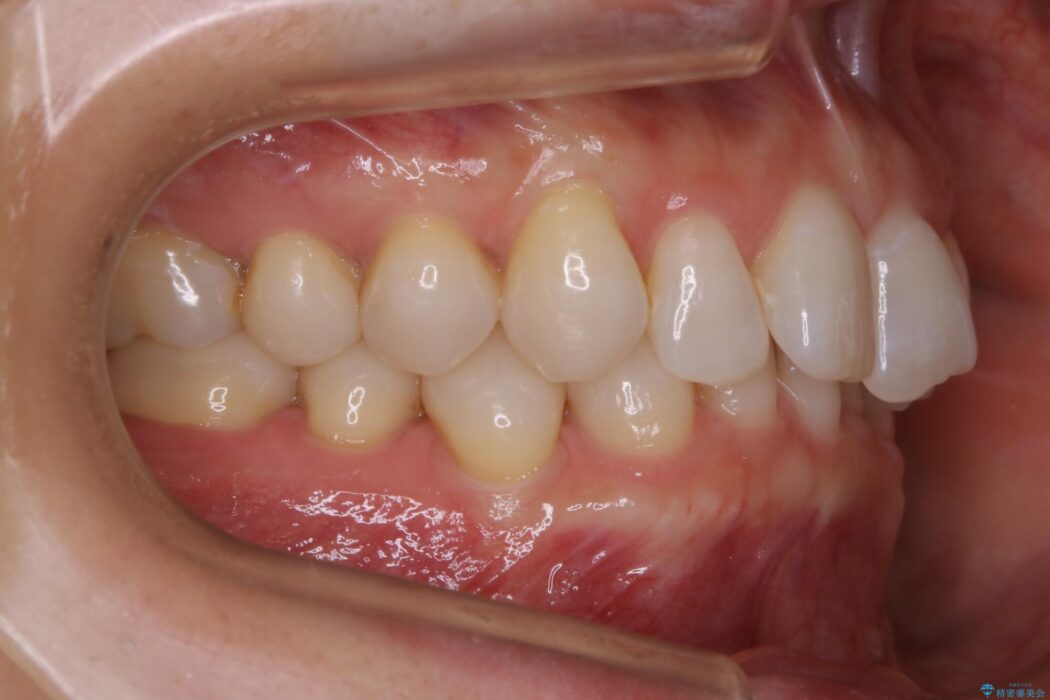

噛み合わせも改善され、一番最初の目的であった歯列もきれいに整いご満足いただけました。